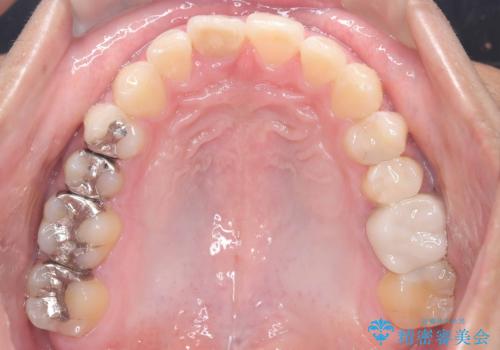

- 「上の前歯の捻じれと下の前歯のでこぼこを治したい」を主訴に来院された患者様です。

矯正検査の結果、非抜歯で矯正可能だったためインビザラインで治療を行いました。

アーチの拡大とIPRで叢生を改善いました。

11ヵ月で矯正を終える事ができ患者様も大変ご満足されていました。